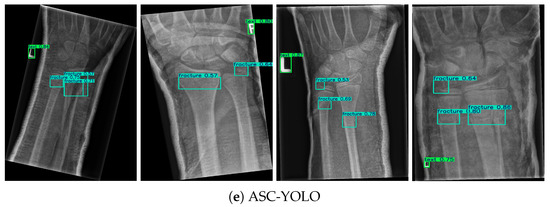

ASC-YOLO: Multi-Scale Feature Fusion and Adaptive Decoupled Head for Fracture Detection in Medical Imaging

3. Results

| ASC-YOLO | 2.9 | 0.550 | 0.602 | 0.412 |